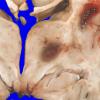

Granulocytic Sarcoma (3)